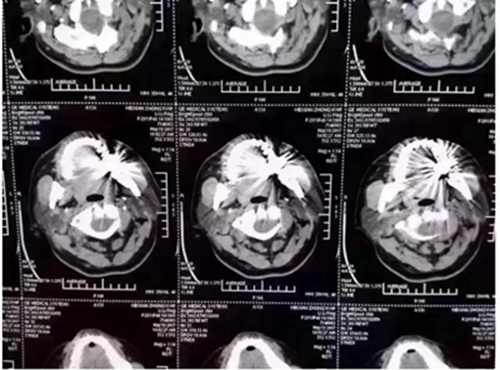

這幾天,一張照片刷爆了牙醫(yī)朋友圈

對(duì)這張照片,有牙醫(yī)評(píng)論如下:

口內(nèi)有金屬烤瓷牙做核磁共振,CT,以烤瓷牙為中心呈現(xiàn)放射狀影像,無法看清周圍組織,影響臨床診斷,建議條件允許的朋友還是選擇二氧化鋯全瓷冠修復(fù),以免帶來不必要的麻煩!

另外,非金屬的二氧化鋯對(duì)X線卻無任何阻擋,只要鑲?cè)攵趸喛敬裳?,日后做頭顱X線、CT、核磁共振檢查時(shí)都不需要拆掉假牙,省去很多麻煩。本文之前曾報(bào)道《牙齒阻礙磁共振?那是你沒有用二氧化鋯牙》

2.因金屬內(nèi)冠的存在,透光性、色澤和形態(tài)與自然牙存在較大的區(qū)別,更會(huì)在燈光下產(chǎn)生青灰色的效果。同時(shí)金屬瓷牙在液體口腔酸堿環(huán)境細(xì)菌作用下不穩(wěn)定,患者在做CT核磁共振時(shí)金屬有一定的干。